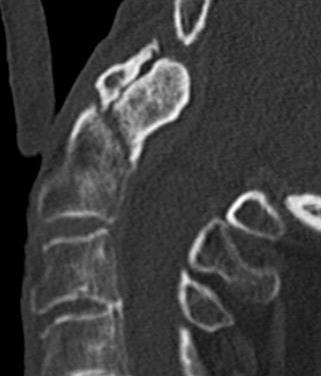

Superior projecting bony element of C2 / axis

C1 / atlas rotates around the dens to provide cervical rotation

Type 2

Fracture of base of odontoid process

- most common type

- > 50%

Type II Dens Fracture

Issue

Stability

Union